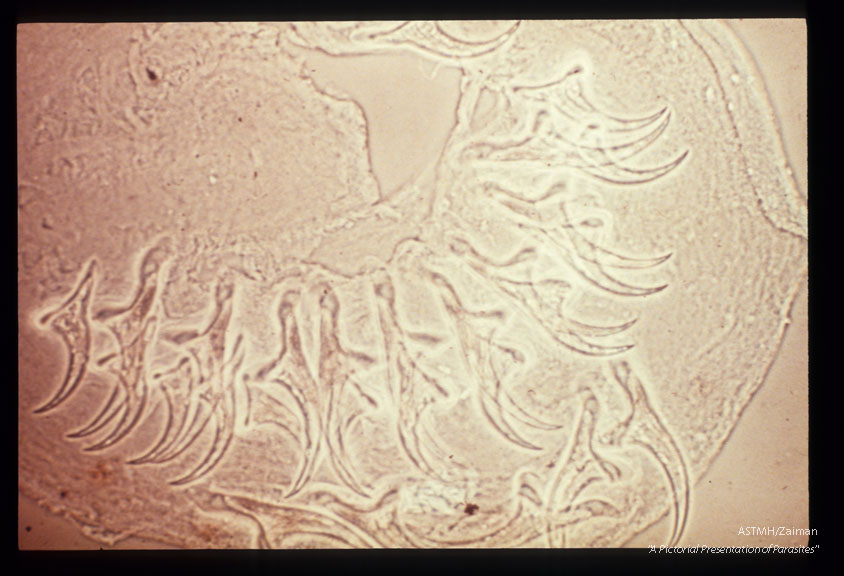

Hooks from same parasite.

Taenia crassiceps

Description: Hooks from same parasite.